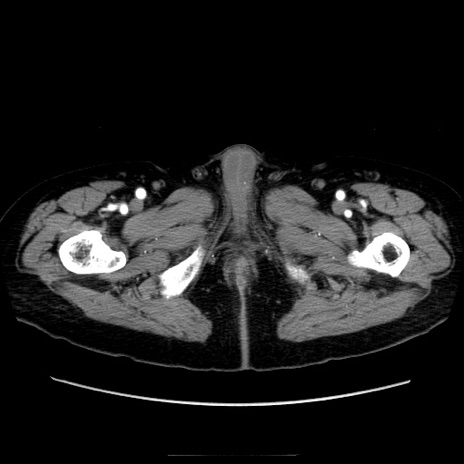

【症例】70歳代男性

【現病歴】肝硬変・肝細胞癌にてかかりつけの方。約9時間前に食後より腹痛出現。症状が徐々に増悪し、嘔吐出現したため来院。

【既往歴】肝硬変、肝細胞癌(RFA、TACE後)